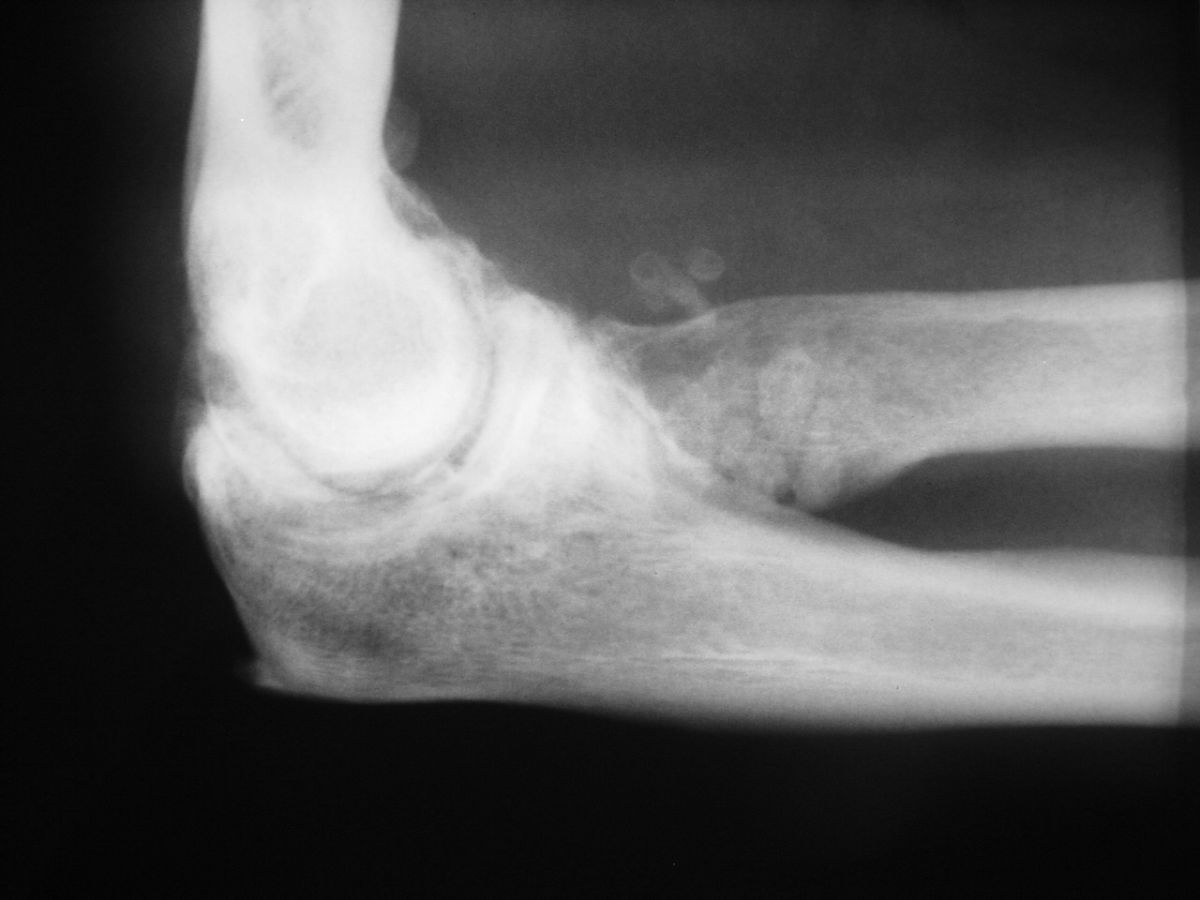

| Case 2. This 74 year old man presented with elbow pain years after wide excision of the central ulna and forearm radiation for a malignant tumor. The abnormal load on the radiocapitellar joint has resulted in degenerative changes. |